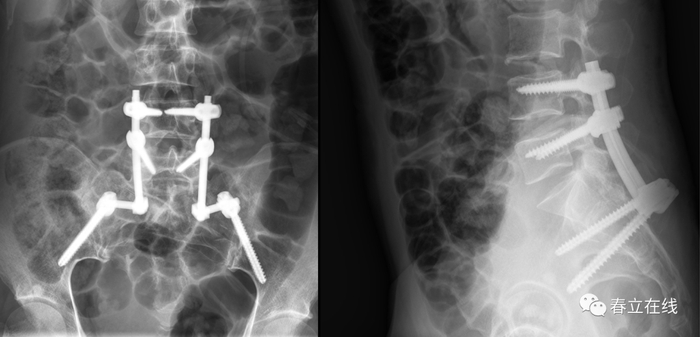

病例1

病例2